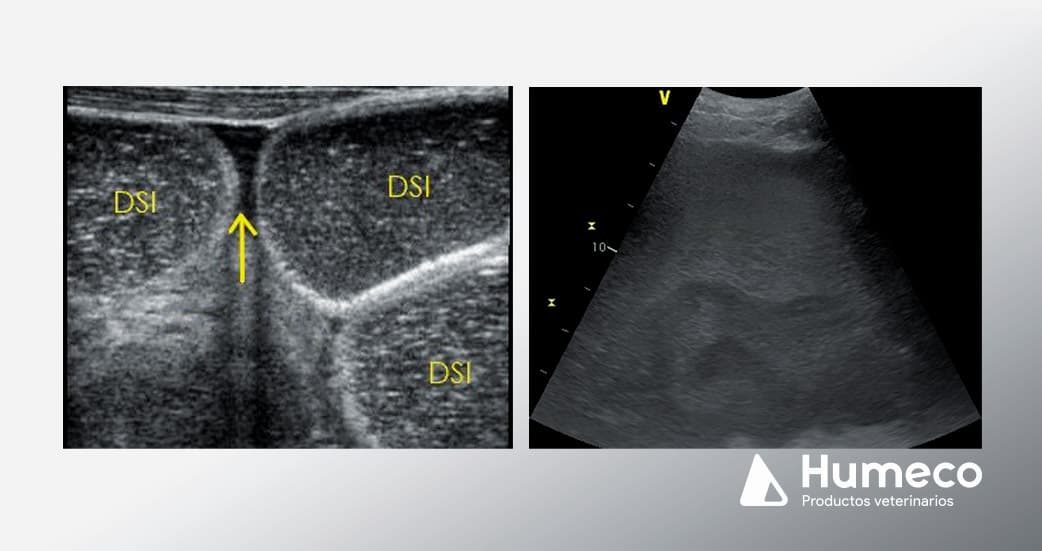

Colocar la sonda a la altura del esternón en la línea media ventral y desplácese hacia abajo. Las asas normales del intestino delgado están colapsadas o ligeramente distendidas y suelen identificarse en la profundidad del bazo y en la región inguinal. El colon grueso se localiza en la parte ventral del abdomen. Las lesiones de estrangulamiento del intestino delgado se asocian a asas de intestino delgado distendidas (DSI) y amótiles, que suelen identificarse en el abdomen caudoventral (imagen 1). Las asas normales del intestino delgado suelen visualizarse como múltiples densidades redondas y móviles, sin distensión.